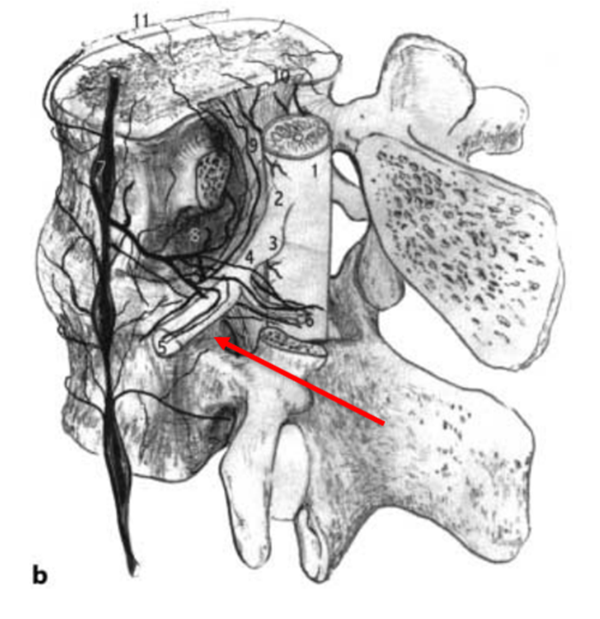

图6

无论是RN入路还是SP入路,两种注射方法均是把药物注射至神经根的背侧或侧方,而通过对神经解剖学的认知,人们认识到,为了缓解神经疼痛,需要把药物注射至腹侧硬膜外间隙,即椎间盘/硬膜交界处、椎弓根的内侧,使得药物覆盖神经根,才能更为有效。所以,最理想的方案应该是把穿刺针通过穿刺置于椎间盘的背侧,硬膜囊的腹侧。通过解剖学发现,尽管脊柱通过骨性结构及韧带结构把重要的脊髓神经保护其中,形成一个相对封闭的结构,但仍保留了与椎管相同的孔道,正像圣经中所言:“when God closes this door, he will open another door for you”,而这扇窗,就是椎间孔。

其实早在1973年,Parviz kambin教授就提出了kambin三角,kambin三角较Bogduk三角拥有更大的空间结构,能有效避开重要的神经和血管。因此,利用Kambin三角进行穿刺,将穿刺针尖置于病变间隙硬膜囊腹侧,同时具备了安全和有效的特点。Jasper JF于2007年介绍了这种方法,他将这种方法称之为Retro-discal approach(RD)入路。Jasper认为,一个最佳的注射位置应该是使得药物覆盖椎间盘病变区、椎间盘神经界面和受刺激的节段性神经。这种穿刺方法同时也是经皮椎间孔镜置入工作通道的路径,更为外科医生所熟悉,也使得“经椎间孔注射术”名副其实。该方法成为了脊柱外科医生、疼痛科医生和神经外科医生最为推崇和认可的穿刺方式。在2014年,NASS把经椎间孔注射术写入了《腰椎间盘突出症诊疗指南》中,推荐等级为A级。

图7